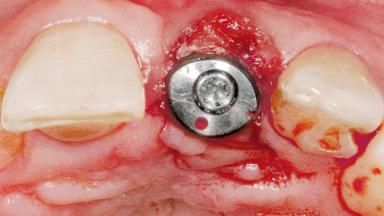

Late Flapless Placement of an Implant in a Maxillary Left Central Incisor Site

A 39-year-old male patient presented with a chief complaint of discomfort and gingival discoloration around his maxillary left central incisor. He was in good general health and was a non-smoker. His past dental history was significant because of the traumatic fracture of tooth 21 in a sporting accident at age 13. Initial dental treatment included endodontic therapy and a full-coverage restoration. The patient became symptomatic 5 years later, when structural failure of the tooth resulted in the dislodgment of the crown. Endodontic retreatment, apical surgery, and post-and-core restoration were performed.

Type of Implants One-Piece

Attachment One-Piece